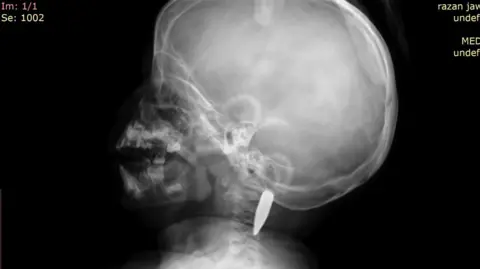

Razan, la petite fille, a été gravement blessée lorsque la balle a ricoché à travers le corps de sa mère avant de se loger dans son cou, à quelques millimètres de sa moelle épinière. David Anderson, âgé de 55 ans et originaire d’Écosse, a décrit la situation comme étant un véritable miracle, compte tenu de la proximité de la balle avec des zones vitales.

Scanner CT montrant la balle dans le cou de la fillette